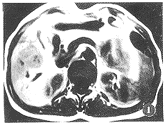

3頭顱CT掃描